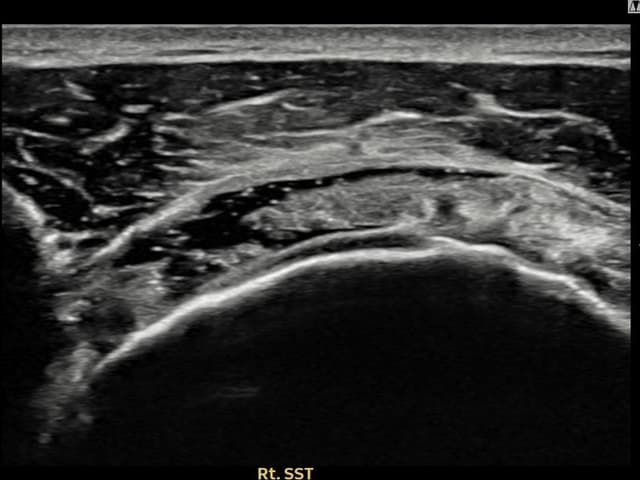

実際の患者様の施術前後の超音波画像。

手術なしで実現できる回復をご確認ください。

[経過期間: 23.09.01~23.11.03]

[縫縮術] 超音波検査にて右 棘上筋腱 滑液包面側部分断裂(8mm × 4mm (腱厚の約35%欠損))を確認。縫縮術施行後、腱の連続性が回復し、日常生活に復帰されました。